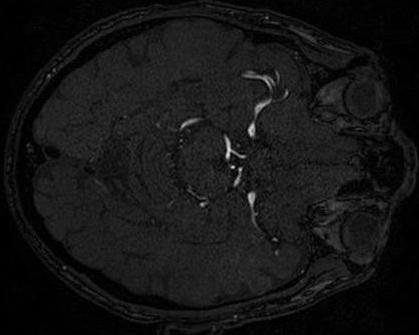

4.4 Qualitative Results

We show sample visual results of representative slices in Figure 3. Sample 3D visual results are given as surface renderings of segmentation maps in Figure 4.

| Baseline GAN | sGAN | Ground Truth | |

|---|---|---|---|

![]() |

|